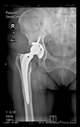

The radiological examination allowed us to verify the close bone-to-implant contact and the unchanged position of the implant during follow-up.

In all the cases operated with the above-described targeting procedure, the stems of the cups remained between the cortical bone surfaces without perforation of the linea terminalis, as shown by postoperative radiographs. There were no complicated surgical situations. In 16 cases, the wound healings were uneventful, and the hips were able to bear weight again after postoperative rehabilitation.

At the time of the manuscript edition, some cases reported in this study were still in the early postoperative period. Even the shortest 10-month follow-up means that patients’ wound healing was uninterrupted, and the implant was securely fixed. By this time, patients are beyond successful rehabilitation. Of course, as with all such patients, monitoring will continue at annual check-ups. Report on the mid and long-term outcomes, gait analysis, and subjective assessments of patients is planned.